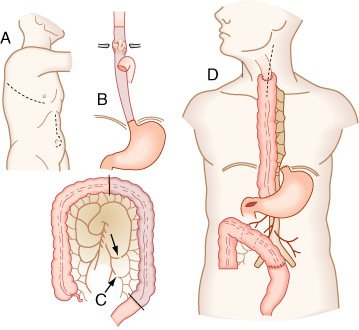

Esofagectomia com interposição de segmento antiperistáltico do cólon. A, Incisões usadas para realizar a esofagectomia, esofagostomia cervical, piloromiotomia e gastrostomia. B, Extensão da ressecção esofágica (área sombreada). C, Preparo do segmento de cólon esquerdo (área sombreada) para interposição baseada na artéria cólica média (perceba os locais de interrupção da vascularização, que preservam a integridade da arcada vascular). D, Operação completa.